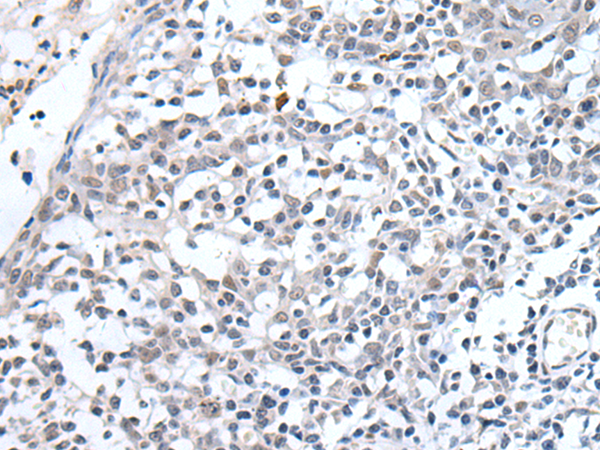

ELISA, IHC |

IHC positive control: |

Human breast cancer and human tonsil |

IHC Recommend dilution: |

10-50 |